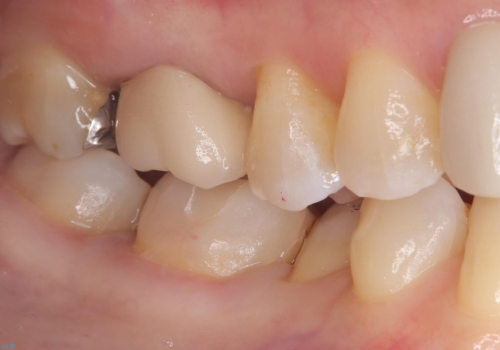

- 主訴:口を開けると所々入っている銀の詰め物が目立つので白い物にやり替えたい。

下顎大臼歯部に入っている保険適用のメタルインレーを、適合性と審美性の良いセラミックインレーでのやり替えとなりました。

メタルインレーを除去した際、古い裏層材やカリエスは除去し新たにCR裏層しています。

セラミックインレーセット時はラバーダム防湿を行っています。